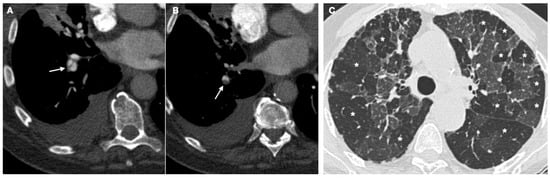

- Sherrick, A.D.; Swensen, S.J.; E Hartman, T. Mosaic pattern of lung attenuation on CT scans: Frequency among patients with pulmonary artery hypertension of different causes. Am. J. Roentgenol. 1997, 169, 79–82. [Google Scholar] [CrossRef] [PubMed] [Green Version]